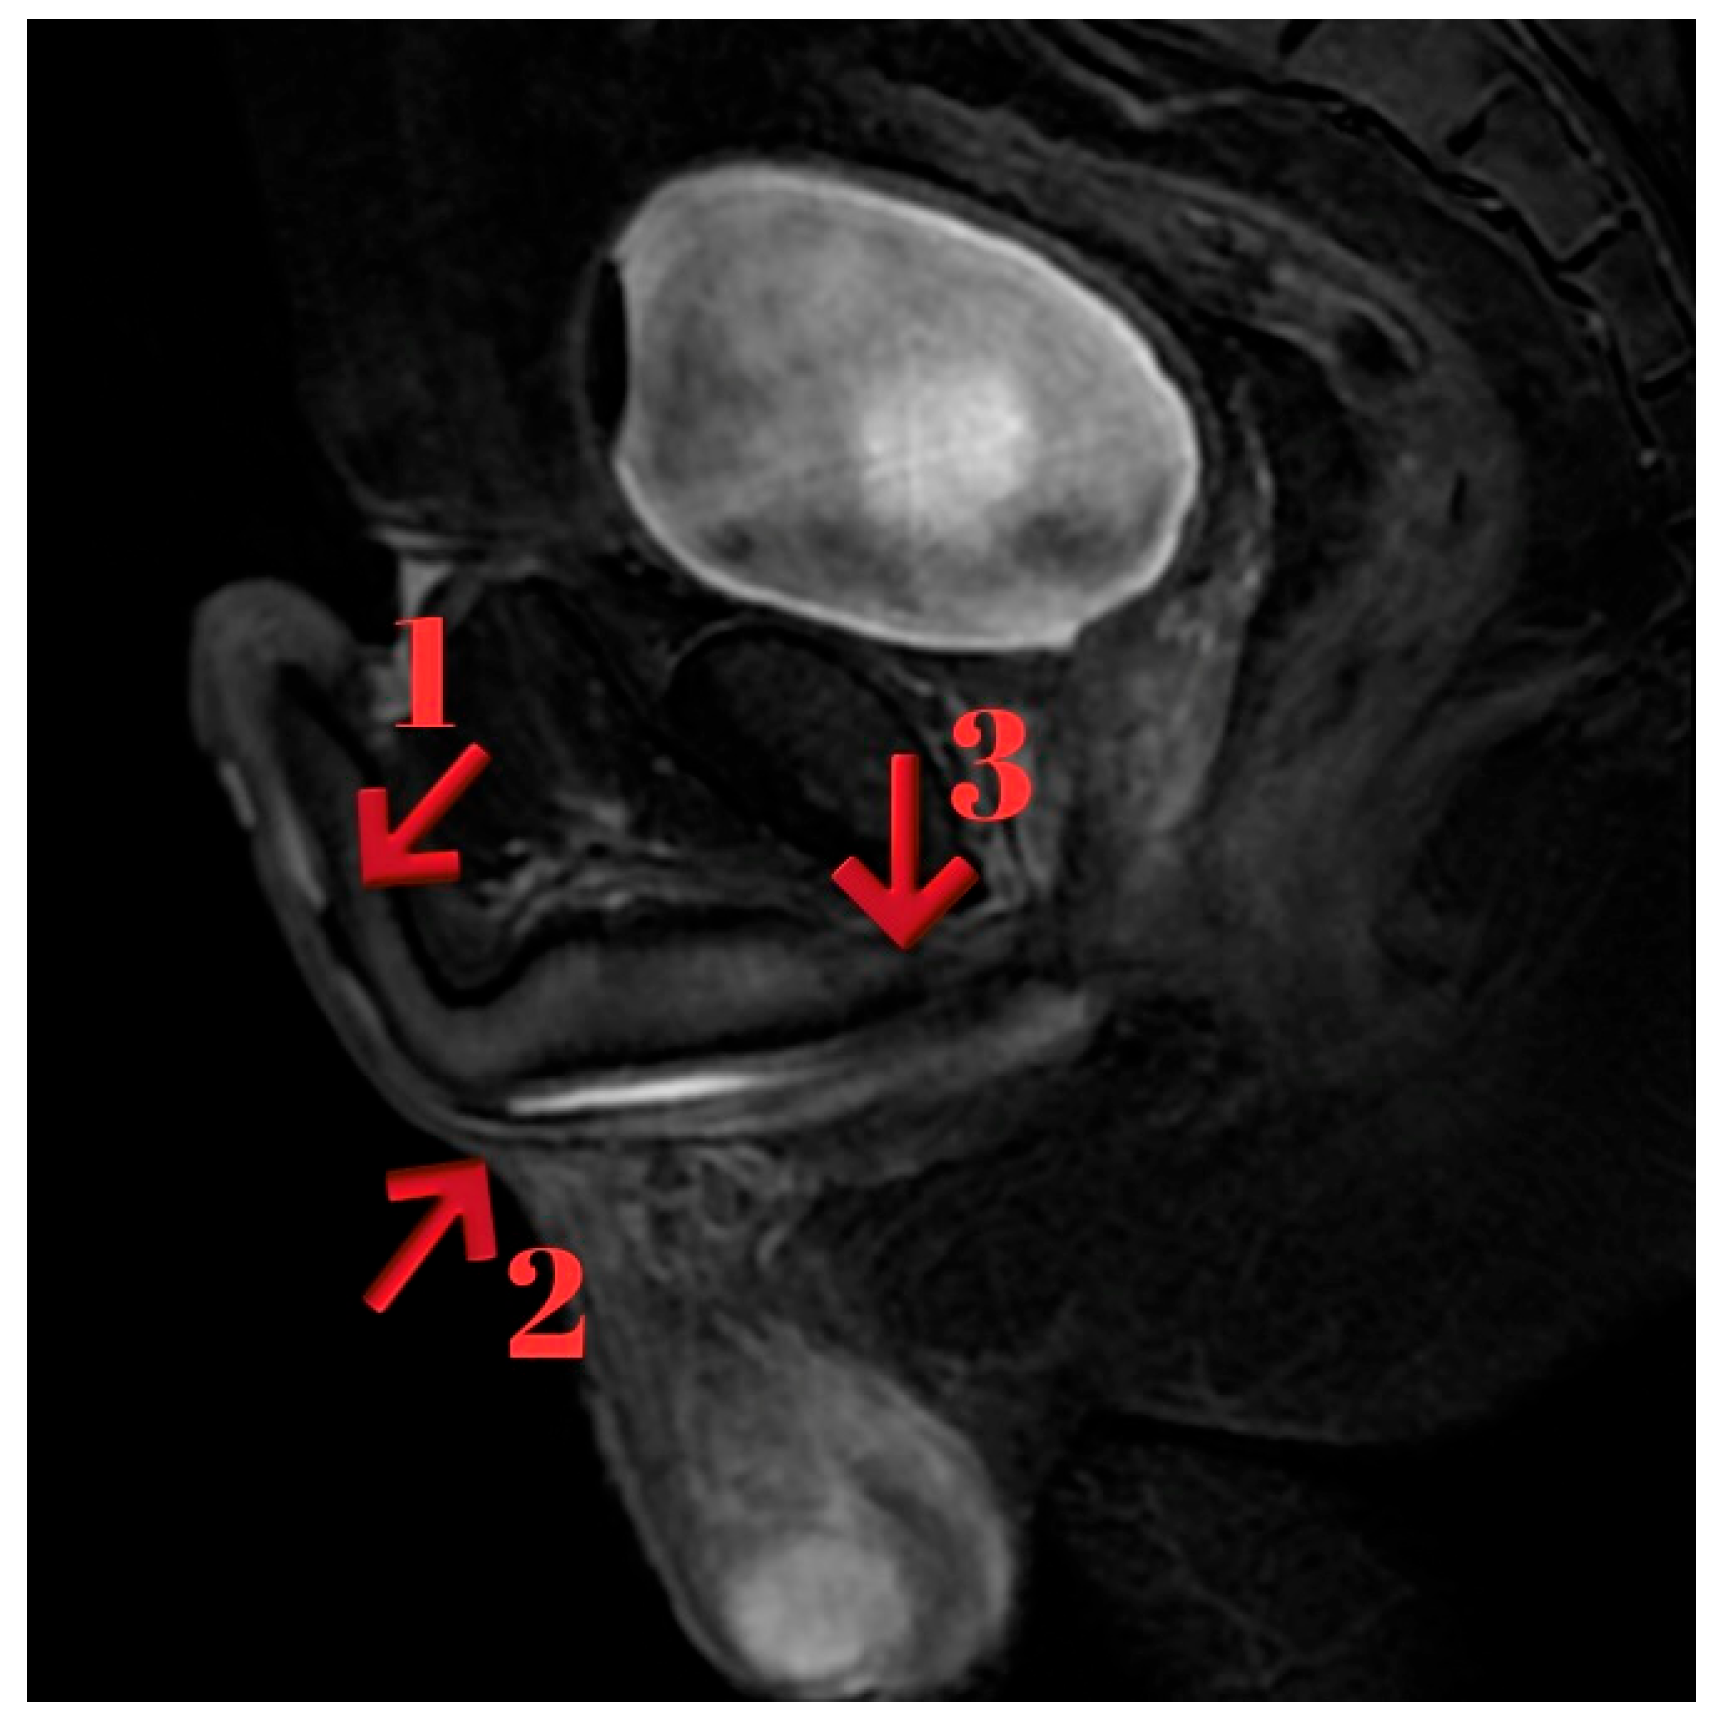

Urethral MRI, performed after bladder filling via the cystofix catheter, demonstrated that the lidocaine gel instilled through the meatus failed to advance through the penile urethra. Two focal fibrotic stenotic-occlusive lesions, each approximately 7 mm in length, were identified at 4 cm and 7 cm distal to the meatus in the distal penile urethra. A 6 mm localized dilatation was noted just proximal to these lesions in the penile urethra. The proximal penile urethra, bulbar urethra, and membranous urethra appeared patent. In the distal segment of the prostatic urethra, inadequate luminal expansion was observed over a 7 mm segment. However, the overall wall structures of the prostatic and membranous urethra were within normal limits. No posterior urethral obstruction was present (Figure 5).

Figure 5. Arrow 1: Completely obliterated distal penile urethral stricture (4 cm from the meatus). Arrow 2: Second completely obliterated stricture located proximally at 7 cm from the meatus. Arrow 3: Additional non-obliterative narrowing within the bulbar urethra, extending toward the sphincter.